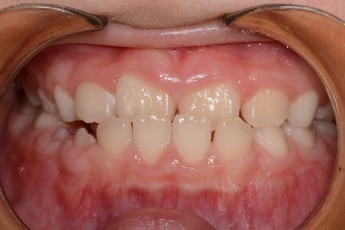

BEFORE & AFTER

- 성장교정